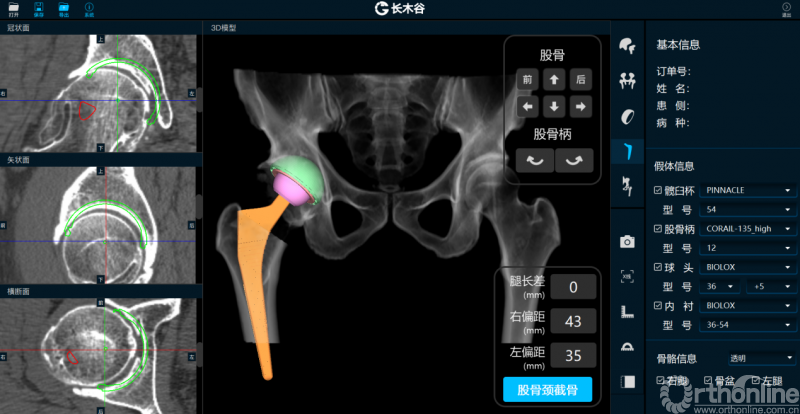

由AI HIP系统对患者的髋关节CT数据进行人工智能分割与关键点识别,术者可根据智能分割与测量结果综合判断患者情况。如图可见,该患者关节内可见明显畸形。

AI HIP系统对患者术前偏距与腿长差进行智能测量与评估

而后,由人工智能判断患者双侧腿长差及股骨偏心距大小,如图可见,由于长期受到的髋关节撞击征影响,该患者术前腿长差为2mm,右侧股骨偏心距为43mm,明显大于左侧股骨偏心距35mm。

AI HIP系统智能安放54mm直径的强生Pinnalce髋臼杯

最后,AI HIP系统根据患侧股骨颈干角、偏心距偏大的特殊情况,智能选择使用高偏高颈干角假体,对下肢等长和等偏心距重建做出了精准设计。根据系统预测结果,术中使用54mm Pinnalce髋臼杯、12号CORAIL高偏股骨柄、36mm 陶瓷股骨头、小转子上23mm截骨,实现髋关节的个体化、精准化重建。